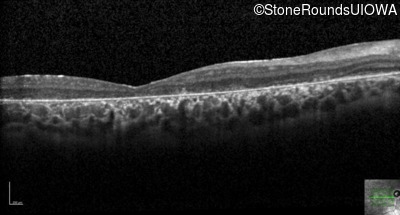

Optical Coherence Tomography - Right - 20/200 sc

Exemplar / OCT Stack